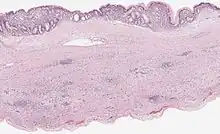

Mucinous cystadenoma of the pancreas 6

Cystic lesions of the pancreas are a group of pancreatic lesions characterized by a cystic appearance. They can be benign or malignant.